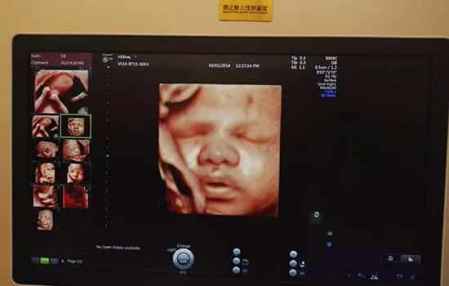

通常情况下,兔唇是能在孕检是被**出来的。但若在**时,胎儿用手当着脸面部或者胎儿与**对着脸,就看不清胎儿是否兔唇。而且部分胎儿可能受到孕妇本身的身体状况,仪器的性能、医生的个人能力等影响,导致**不出兔唇。所以有此担忧的孕**在做排畸**时一定要仔细再仔细!

兔唇的**是通过B超或是四维彩超检测的,孕期月份越大,**的结果越准确,像三个月胎儿较小,想**出兔唇是比较困难的,所以一般在怀孕四个月后才去**兔唇。而且在整个孕期中孕妇需要做大排畸和小排畸**,孕**只要跟着**流程走,一般会及时**出兔唇的。